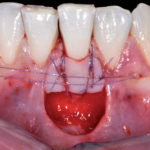

Innesti epitelio-connettivali eseguiti nell’arcata inferiore

Free gingival graft in the lower dental arch

In caso di recessioni gengivali di elementi dell’arcata inferiore è possibile ottenere risultati estetici soddisfacenti utilizzando l’innesto...